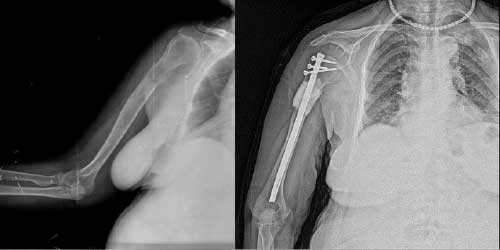

Her ameliyatın olduğu gibi kemik ve yumuşak doku tümör ameliyatlarının da riskleri vardır. Bu riskleri genel ve yapılan ameliyata özgü olmak üzere kabaca iki başlık halinde gruplandırabiliriz. Öncelikle anestezi ile ilgili risklerin anestezi uzmanı tarafından (...)

Ameliyat sonrası takip ve kontrol hastanın ameliyat masasında uyanması ile başlar. Özellikle damar ve veya siniri ilgilendiren ameliyatlarda hasta ameliyat masasından alınmadan ekstremitenin dolaşımı ve ilgili sinirin fonksiyonu kontrol edilir.